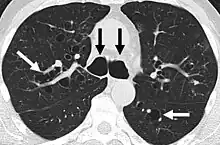

CT scan of the lungs showing findings diagnostic of bronchiectasis. White and black arrows point to dilated bronchi characteristic of the disease.

The goals of a diagnostic evaluation for bronchiectasis are radiographic confirmation of the diagnosis, identification of potential treatable causes, and functional assessment of the patient. A comprehensive evaluation consists of radiographic imaging, laboratory testing, and lung function testing.[64]

A chest x-ray is abnormal in most patients with bronchiectasis. Computed tomography is recommended to confirm the diagnosis and is also used to describe the distribution and grade the severity of the disease. Radiographic findings include airway dilation, bronchial wall thickening, and atelectasis.[66] There are three types bronchiectasis that can be seen on CT scan, namely cylindrical, varicose, and cystic bronchiectasis.[67]